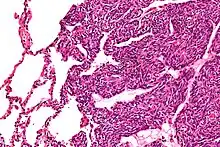

| Micrograph of a monophasic synovial sarcoma. The histologic appearance is non-specific and overlaps with MPNST and fibrosarcoma. H&E stain. | |

Two cell types can be seen microscopically in synovial sarcoma. One fibrous type, known as a spindle or sarcomatous cell, is relatively small and uniform, and found in sheets. The other is epithelial in appearance. Classical synovial sarcoma has a biphasic appearance with both types present. Synovial sarcoma can also appear to be poorly differentiated or to be monophasic fibrous, consisting only of sheets of spindle cells. Some authorities[3] state that, extremely rarely, there can be a monophasic epithelial form which causes difficulty in differential diagnosis. Depending on the site, there is similarity to biphenotypic sinonasal sarcoma, although the genetic findings are distinctive.